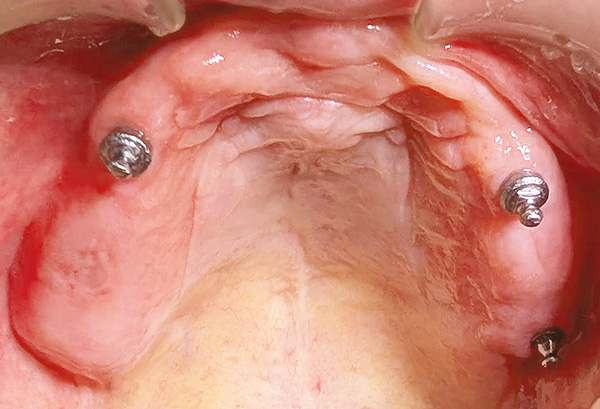

掲載写真撮影:2016年(92歳/女性)|通院歴年|

上顎:インプラント2本植立+総義歯(2003年)、下顎:総義歯(2003年)

こちらも92歳(2016年現在)という年齢以上に健康が維持できていると思われる症例です。「食事では、1回に30~50回噛むことを心掛けてきました」とおっしゃいます。咀嚼することで脳を活性化し、次に脳からの指令により腸内フローラも改善します。また、こなれた食物は効率よく栄養が吸収されます。

この総義歯の固定は、本来の吸着に依存するのでなく2本のインプラントの連結装置定で固定されていますので、上顎の粘膜は、露出し食物の味や温度が自然に感じるようになっています。